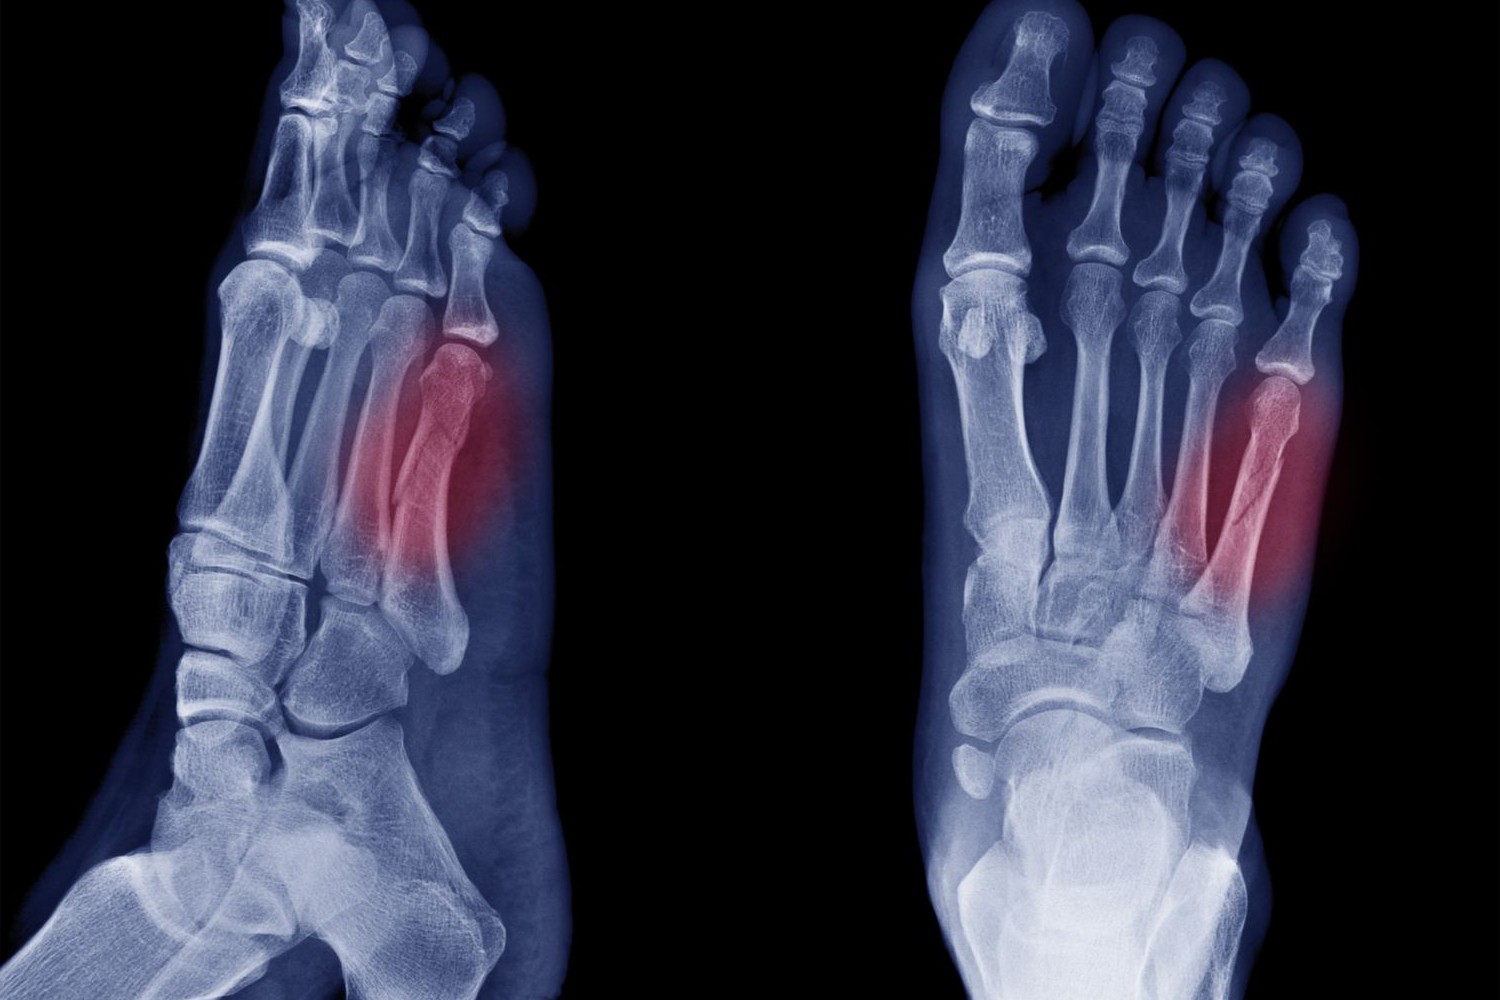

The fifth metatarsal is the most commonly fractured, often due to sports injuries.

Metatarsals are prone to various injuries and conditions, especially for athletes and active individuals. Here are some common issues:

Stress fractures occur due to repetitive stress, often seen in runners.

Metatarsals are among the most commonly broken bones in the foot.